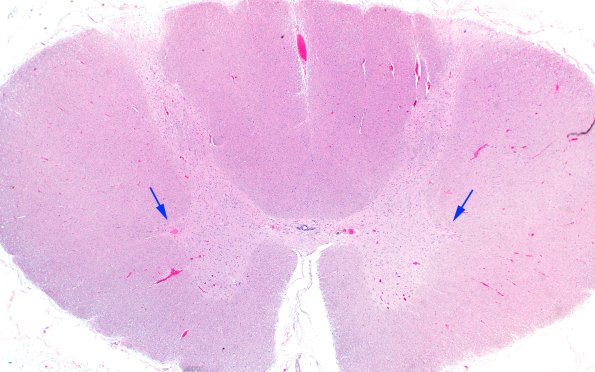

This section of the thoracic spinal cord shows two well populated IML (arrows). (H&E)